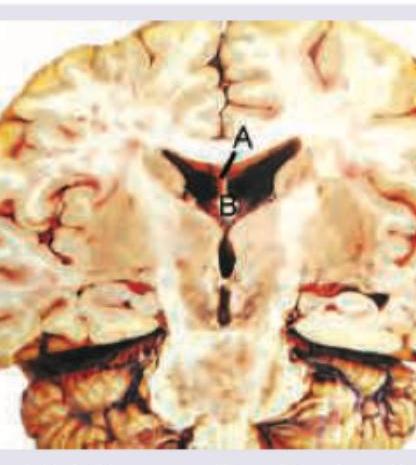

Which is correct about the image shown below?

Explanation: ***A = Septum pellucidum, B= Body of fornix*** - The image displays a coronal section of the brain. **A** points to the **septum pellucidum**, which is a thin, triangular membrane that separates the anterior horns of the lateral ventricles and extends from the corpus callosum to the fornix. - **B** points to the **body of the fornix**, a C-shaped bundle of nerve fibers in the brain that acts as the major output tract of the hippocampus. *A = Choroidal fissure, B= Body of fornix* - The **choroidal fissure** is the gap between the fornix and the thalamus, where the choroid plexus is located; it is not indicated by A. - While B is correctly identified as the body of the fornix, A is clearly a septal structure. *A = Internal capsule, B= Body of fornix* - The **internal capsule** is a white matter structure located deep within the brain, medial to the lentiform nucleus and lateral to the caudate nucleus and thalamus; it is not A. - The structure indicated by A is a thin membrane separating the lateral ventricles, not the dense white matter of the internal capsule. *A = Insula, B= Body of fornix* - The **insula** is a portion of the cerebral cortex folded deep within the lateral sulcus, which separates the frontal and parietal lobes from the temporal lobe; it is not indicated by A. - A is a midline structure, whereas the insula is a lateral structure deep in the cerebrum.